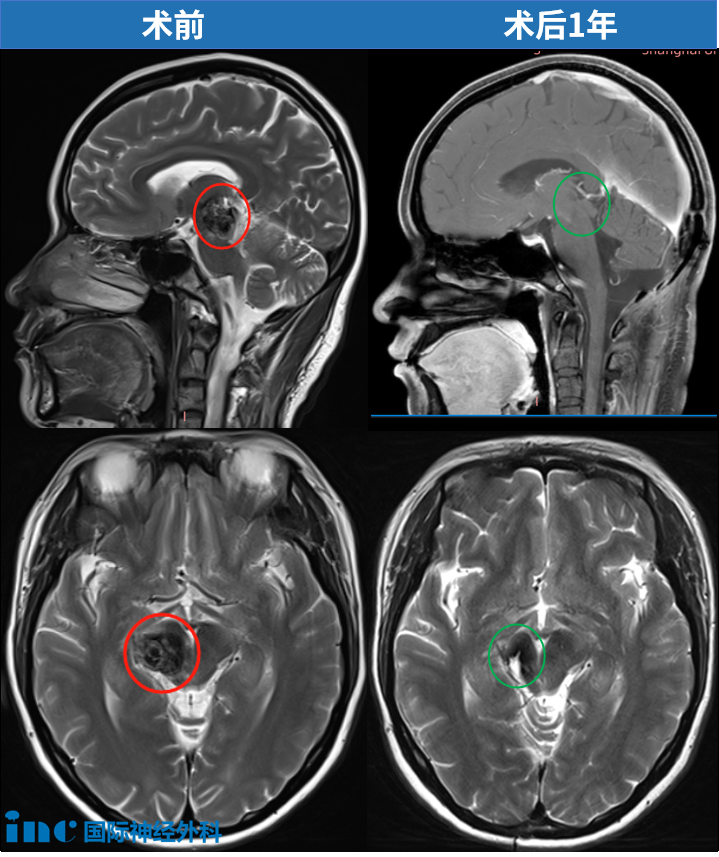

37岁女性丘脑海绵状血管瘤

37岁的思睿,在大家眼中一直是“温暖的小太阳”。2018年,丘脑出血导致思睿复视、记忆障碍、左半身偏瘫,连简单的抓握都成了奢望。医生坦言:“手术风险太大,后遗症可能比现在更严重。”无奈选择保守治疗,直到第2次出血,只能卧床休息时,她感到后怕——“之前是我太轻视了!”最终巴教授为她顺利全切丘脑-中脑海绵状血管瘤,术后第1天四肢活动正常、术前症状缓解。

术后1年,最新核磁显示海绵状血管瘤已被完整切除!视频中她的整体临床状态非常好。巴教授表示在经历过如此巨大中脑/丘脑海绵状血管瘤手术后,能有如此良好的术后恢复,实属罕见!点击阅读:37岁妈妈历时7年战胜“手术禁区”脑干肿瘤,坚持的力量强的没边了!